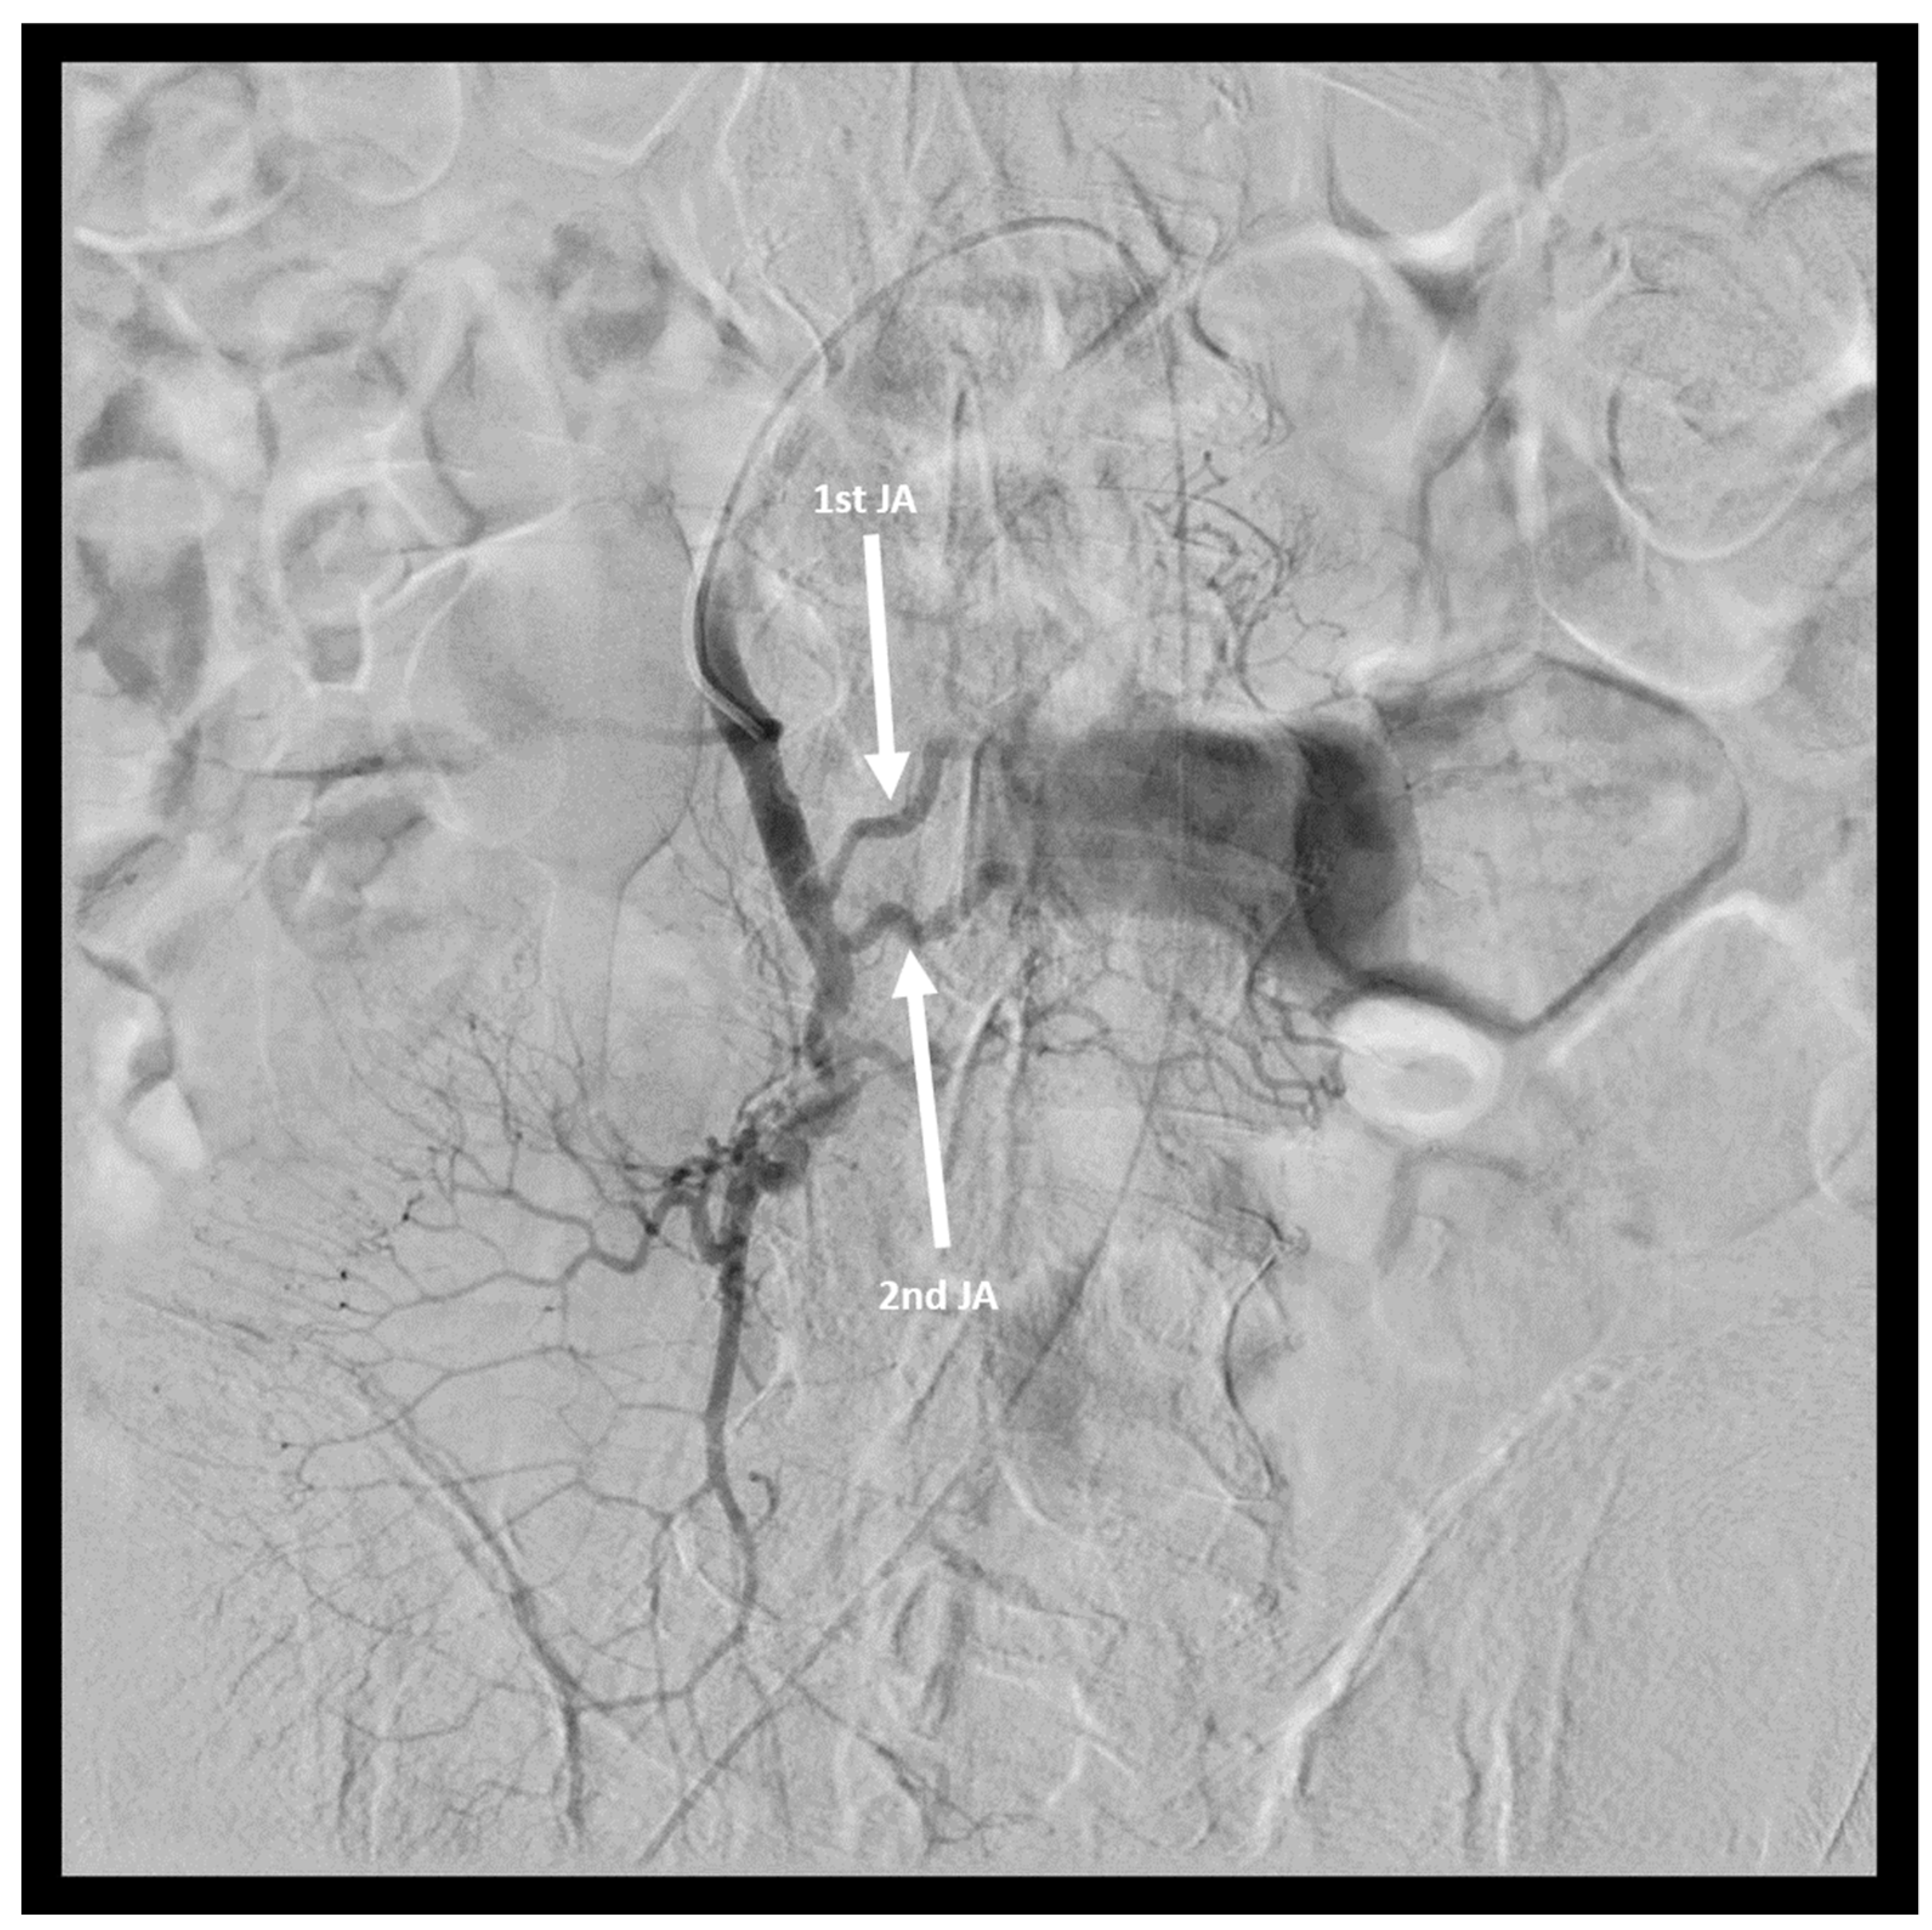

2. Case Report